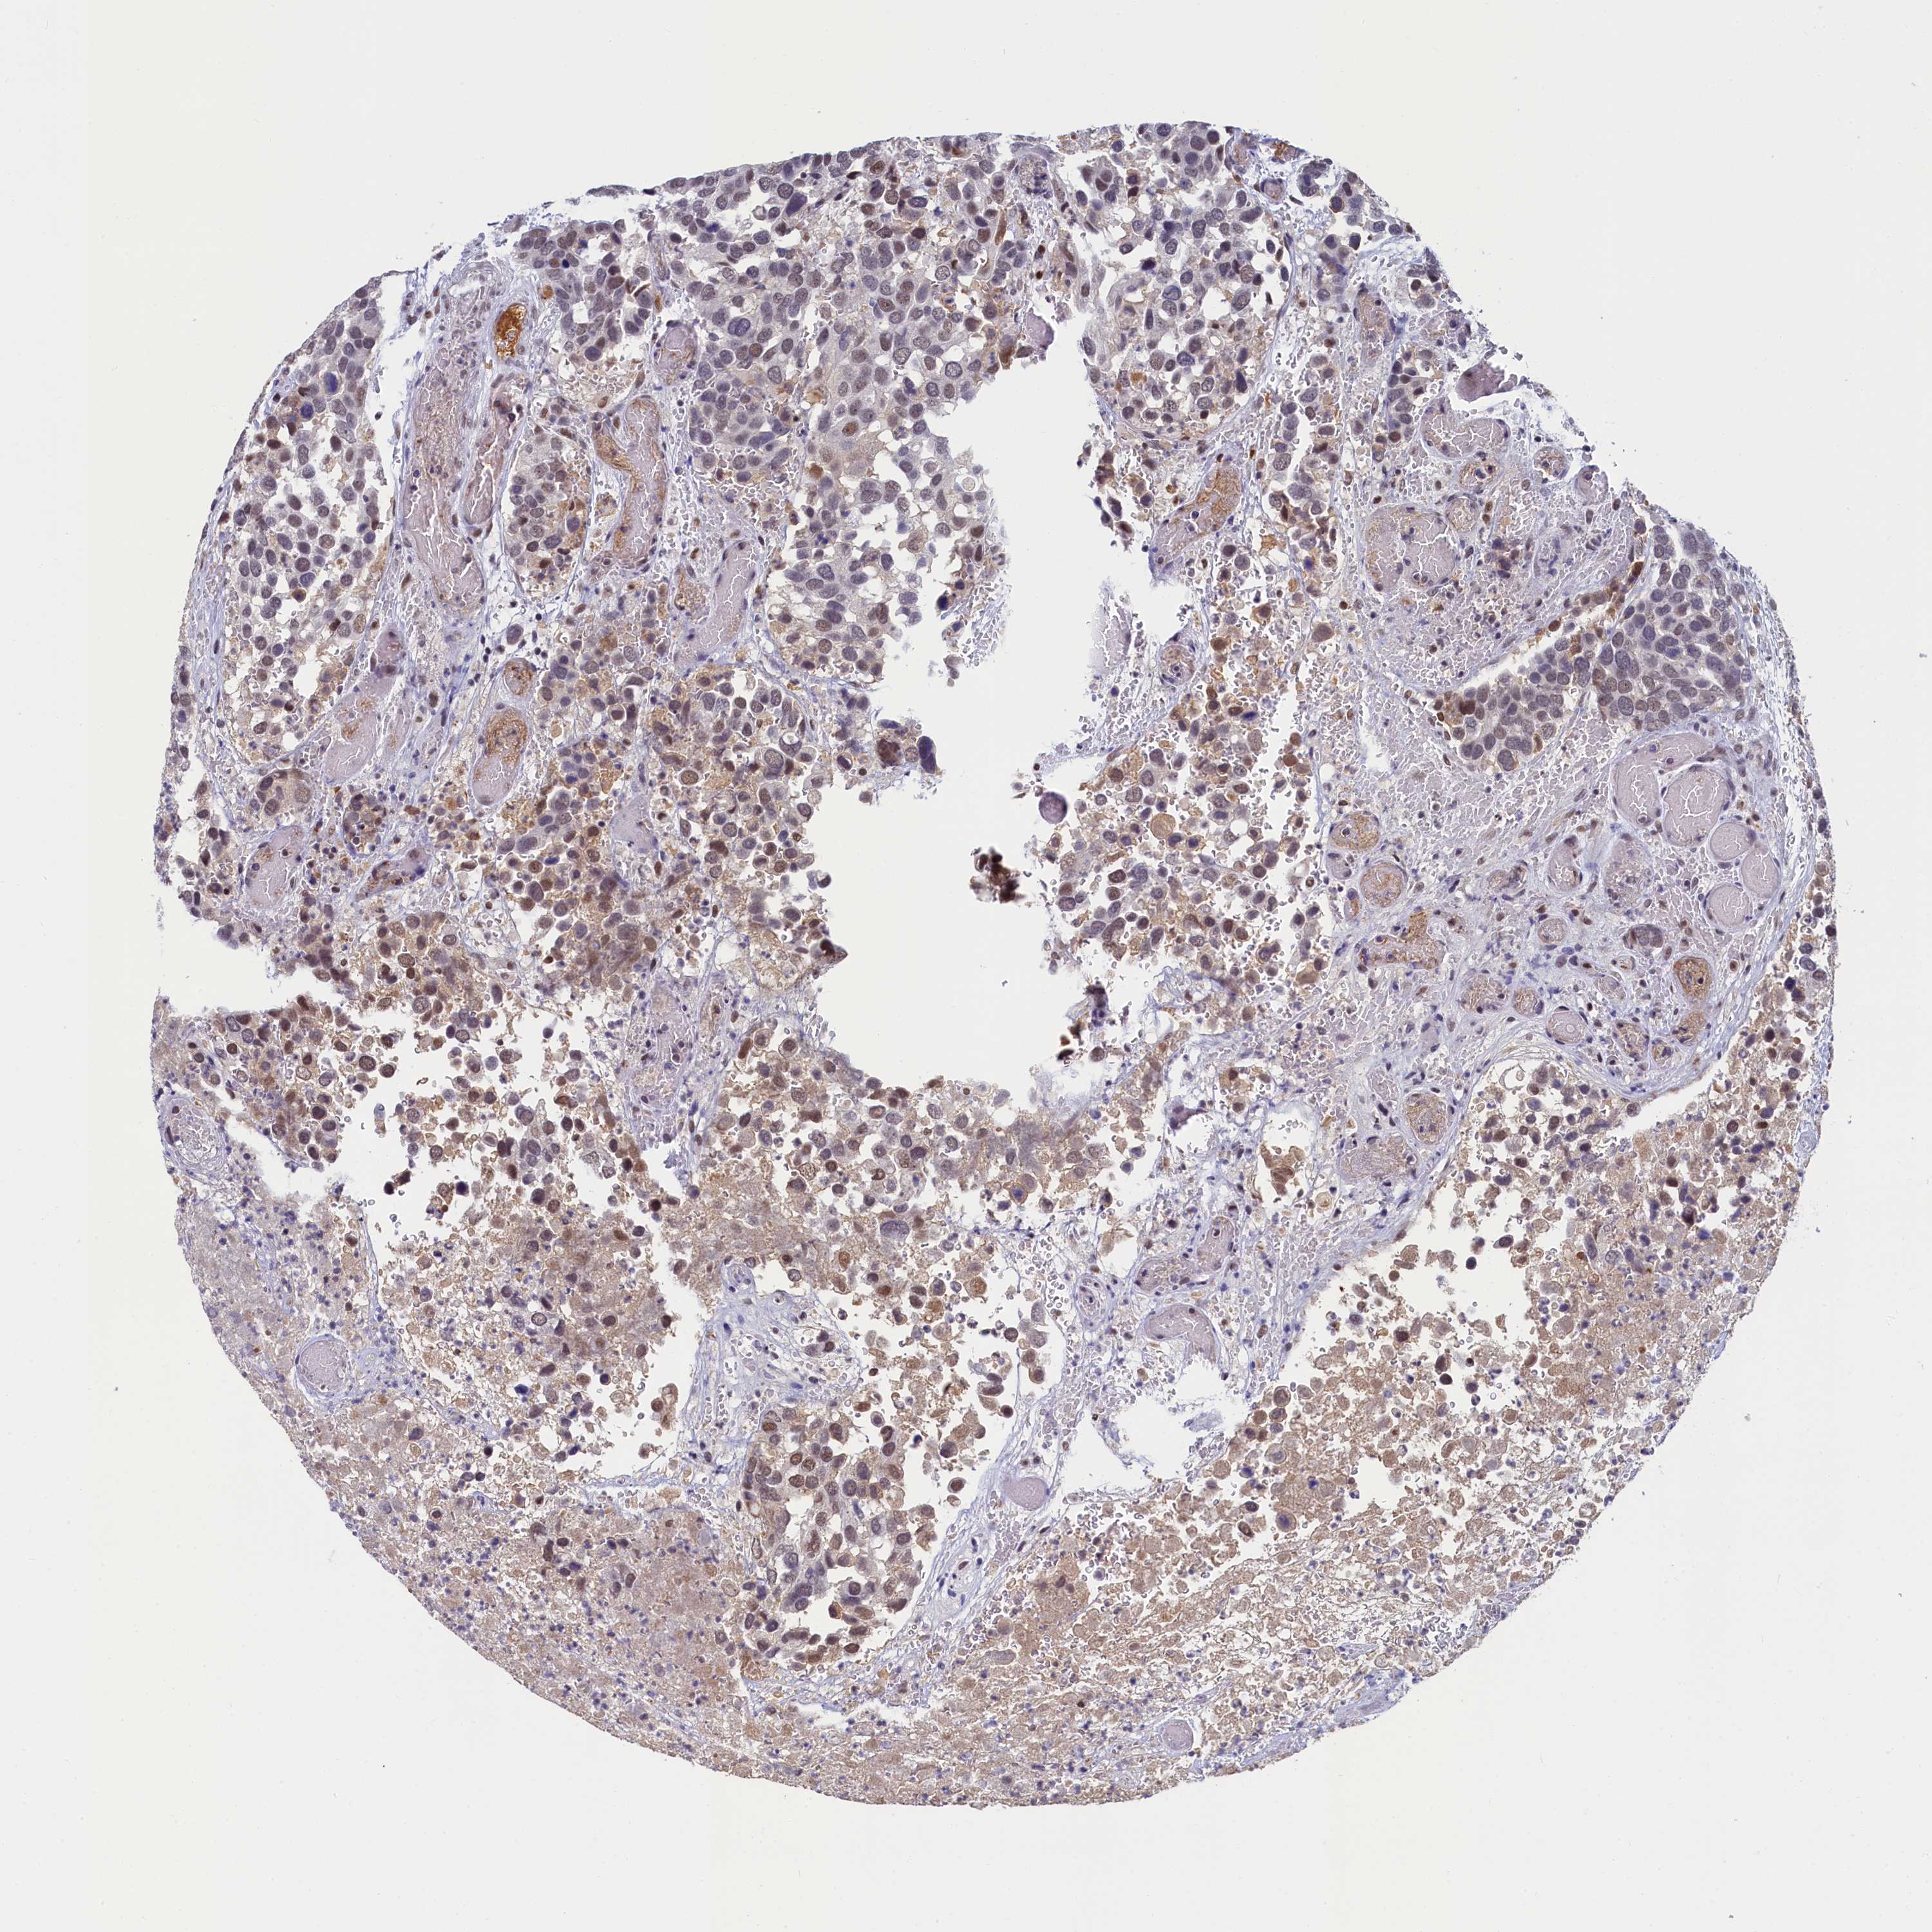

CANCER BREAST CANCER Show tissue menu

BRCA TCGA BRCA VALIDATION PROTEIN EXPRESSION

ANTIBODIES

AND

VALIDATION